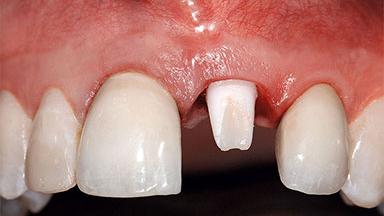

A healthy 37-year-old female patient was referred for a consultation on the replacement of missing tooth 21 with an implant-supported restoration. She stated that several years previously the tooth had been traumatically avulsed following a motor vehicle accident. The tooth was replaced with a three-unit fixed partial denture (FPD) immediately afterwards. Over time, she became disillusioned with the FPD and looked for a different option, including orthodontic therapy. She presented still in her orthodontic appliances, with the pontic sectioned free from the FPD but attached to the archwire. Her orthodontist felt that orthodontic treatment had been successfully completed, but nevertheless referred her before removing the appliances in case adjustments were necessary.

| Abutment Type | CAD/CAM |

| Prosthesis Type | FDP |